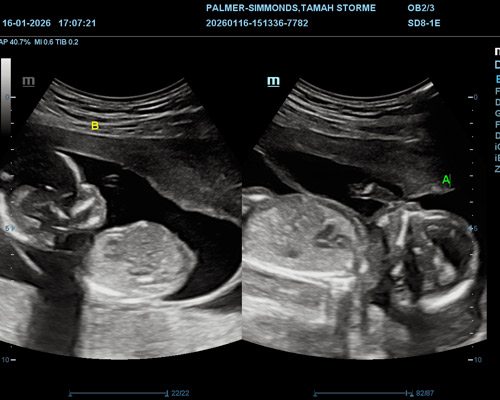

An early twin pregnancy scan near Nottingham allows the sonographer to carefully assess both babies and monitor their development during the early stages of pregnancy. During the ultrasound, important aspects are checked, including:

- The presence of both babies in the womb

- Each baby’s heartbeat and early development

- The position of both babies

- The overall progress of the pregnancy